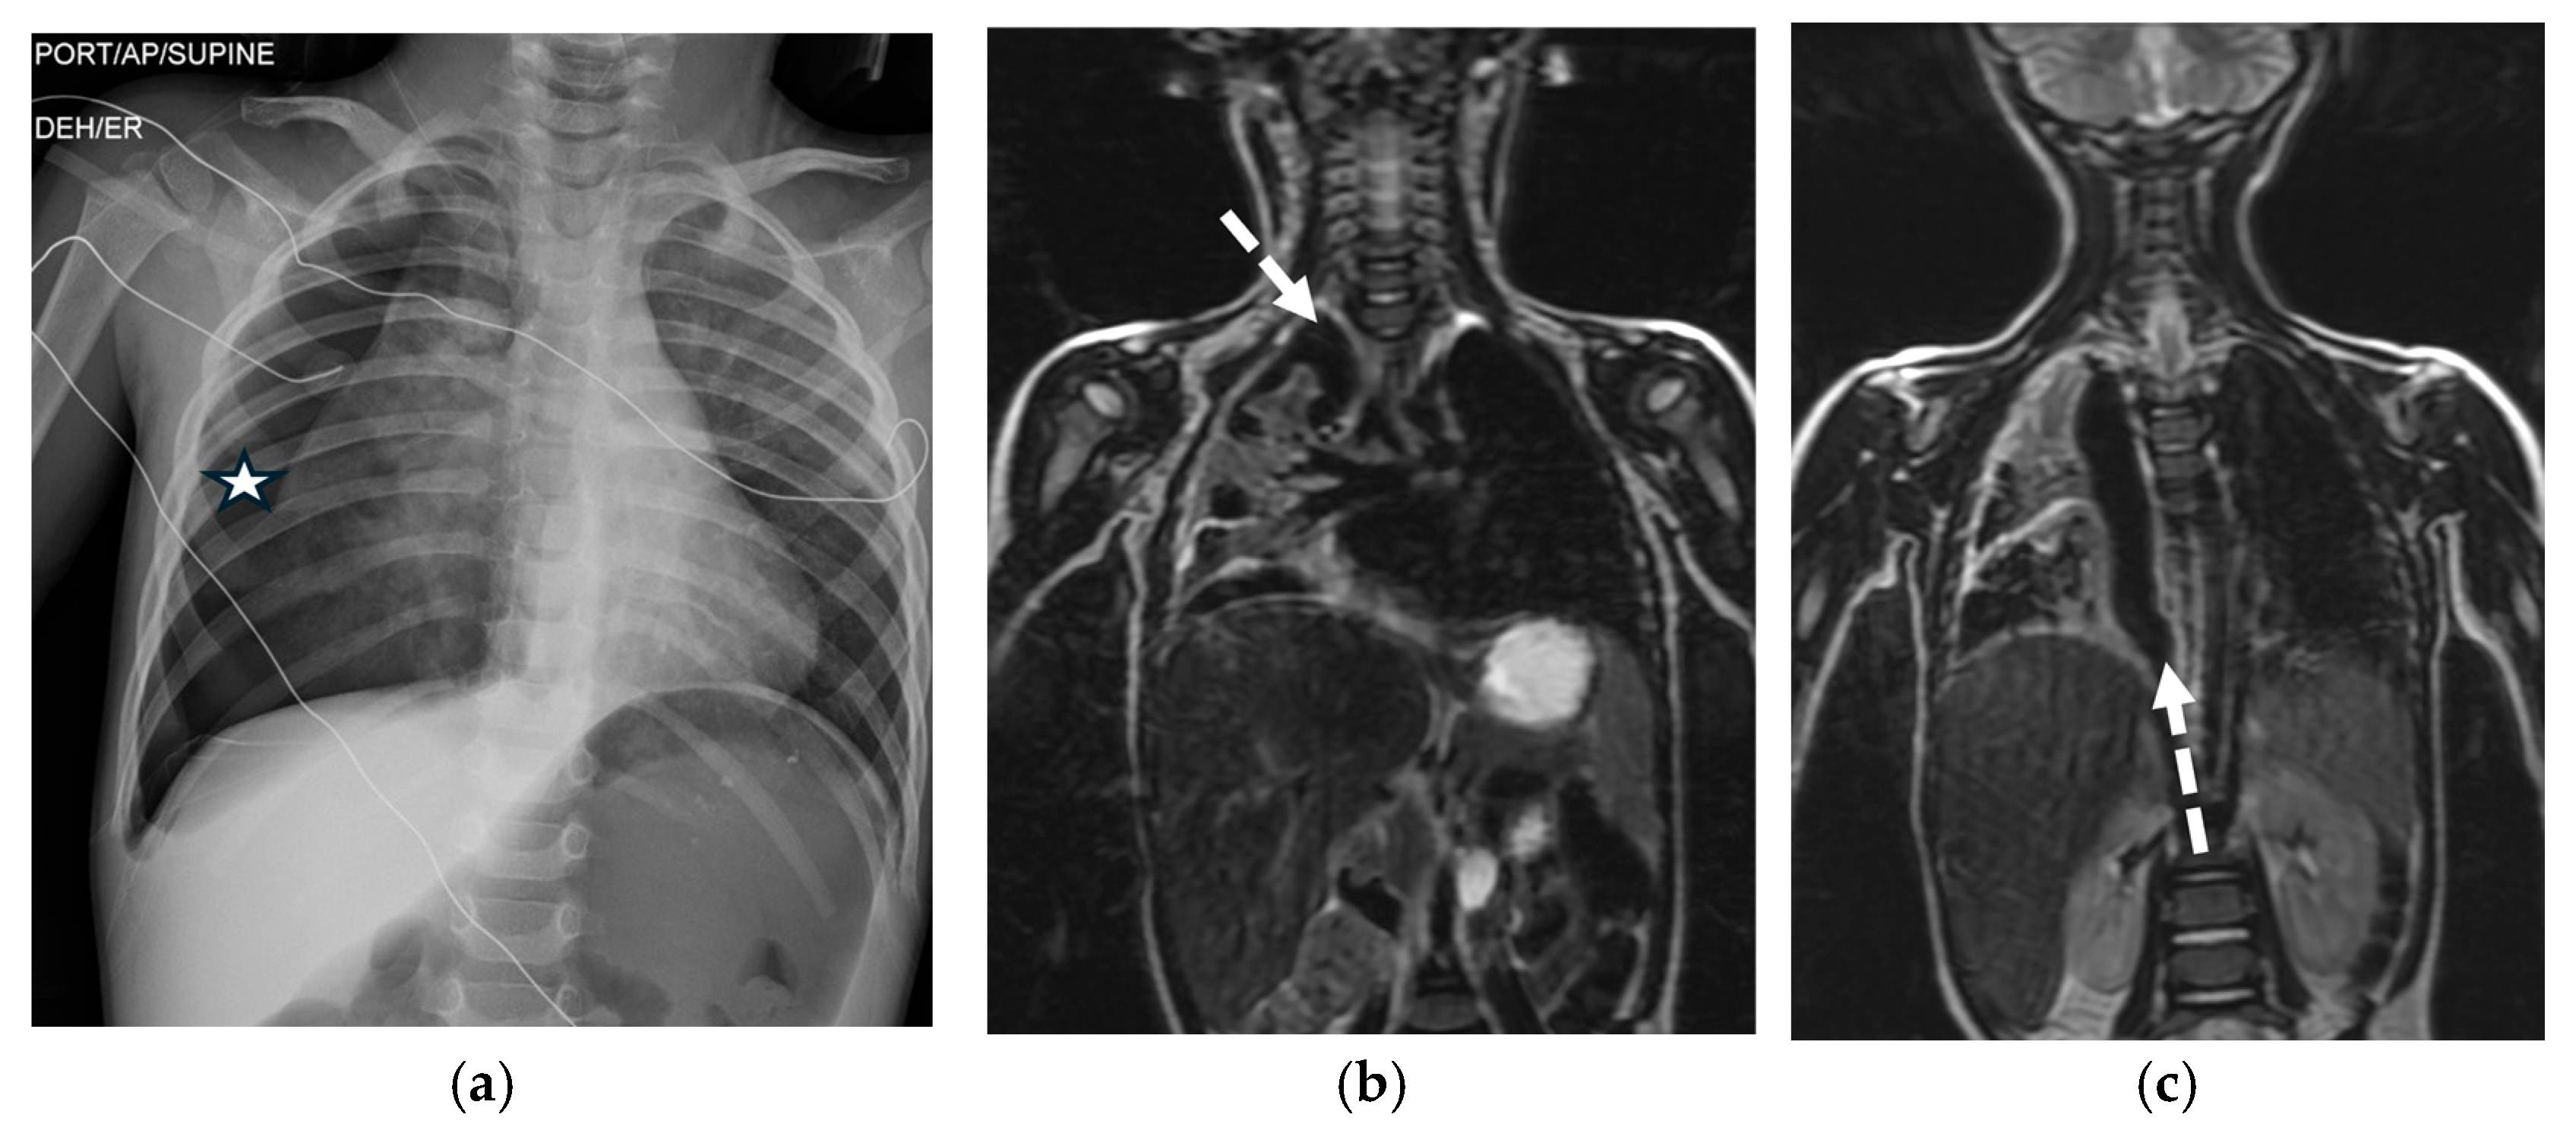

5.7.1. Endometriosis

5.7.2. Electronic-Cigarette or Vaping Use-Associated Lung Injury (EVALI)